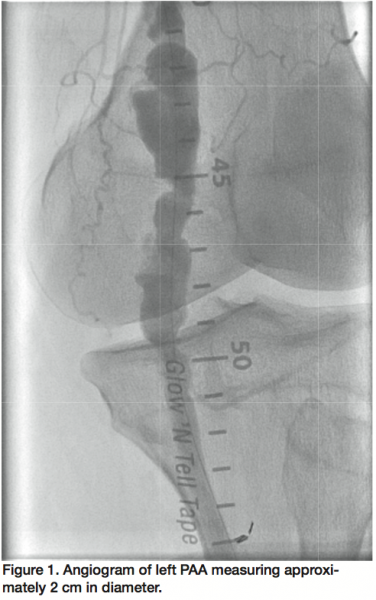

A 64-year-old man was admitted for peripheral angiogram due to symptoms of bilateral lower extremity lifestyle-limiting claudication. Selective angiogram of the left lower extremity showed a heavily calcified mid to distal SFA with 80% diffuse, ulcerated stenoses, and a 2 cm PAA with 3-vessel runoff (Figure 1). Percutaneous intervention of the SFA was performed with Turbohawk directional atherectomy (ev3 Endovascular, Inc.) in the SFA followed by balloon angioplasty with good angiographic result. The PAA was then successfully excluded by deployment of a 7 x 150 mm Viabahn stent (Gore Medical), which was postdilated with a Sterling 7 x 100 mm balloon (Boston Scientific). A Supera 6 x 120 mm, self-expanding, high radial strength stent (IDEV Technologies Inc.) was then deployed within the Viabahn stent (Gore), covering the distal and proximal landing zones in order to reinforce the covered stent. There was a good angiographic result with brisk flow and preserved 3-vessel runoff (Figure 2). The patient was discharged home the following morning and had no complications in 3 months of follow-up.

We have instituted a novel treatment of PAA by first excluding the aneurysm with a Viabahn covered stent (Gore), and then reinforcing and increasing the radial strength of the stent graft by deploying Supera stents (IDEV) within the Viabahn (Gore), covering both the proximal and distal edges across the joint. Our hypothesis is that a covered stent with higher radial strength may lead to improved outcomes in vessel patency, lower incidence of stent thrombosis, and therefore, reduced repeat intervention for limb ischemia. Further investigation with medium- and long-term follow-up will be required before wide acceptance of this treatment strategy for PAA.